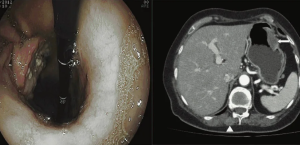

Наряду с уже распространенными методами медицинской визуализации, такими как рентгеноскопия, ФГДС, УЗИ и КТ, при заболеваниях желудка в последнее время все чаще используется МРТ (пока на втором этапе диагностического алгоритма). Основной задачей МРТ является, прежде всего, оценка степени изменения стенки желудка, стадирование патологического процесса с обнаружением как местных, так и отдаленных метастазов.

После введения контрастного препарата «Магневист» определяется неравномерное повышение интенсивности сигнала от образования желудка по периферическому типу.

Визуализируется поражение не только брюшного отдела пищевода, но и дистальной трети его грудной части с признаками стеноза.